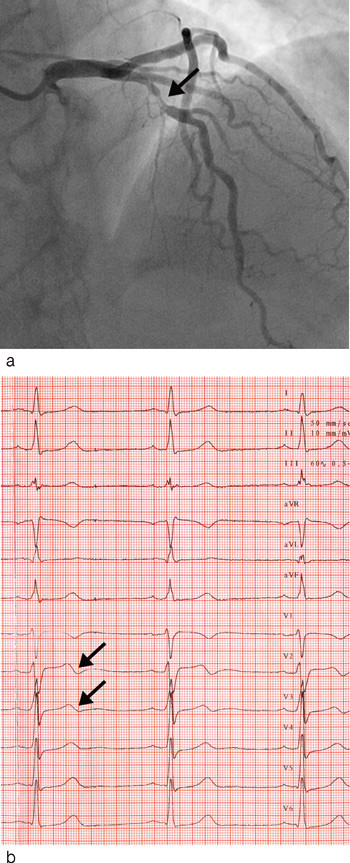

Negativ eller bifasisk T-bølge i V₂ – V₃ ble funnet oftere hos pasienter med iskemirelatert stenose i proksimalt i LAD enn hos de øvrige pasientene med akutt koronarsyndrom (76 % mot 11 %, p < 0,01) (tab 2, fig 1). Blant pasientene med negativ eller bifasisk T-bølge i V₂ – V₃ var det 61 % som hadde iskemirelatert stenose proksimalt i LAD. TIMI-risikoskår, maksimal troponin T, tid etter hospitalisering eller tid etter siste smerteanfall var ikke signifikant forskjellig mellom pasienter med og uten stenose proksimalt i LAD (tab 2). Heller ikke mellom pasienter med negativ eller bifasisk T-bølge i avledning V₂ – V₃ og de øvrige pasientene var det signifikant forskjell i disse variablene.

Bifasisk T-bølge ble funnet hos i alt 13 pasienter, og 11 (85 %) av disse hadde iskemirelatert proksimal stenose i LAD. Negativ T-bølge i V₂ – V₃ ble funnet hos 18 pasienter der åtte (44 %) hadde iskemirelatert stenose i proksimale LAD.

Negativ eller bifasisk T-bølge i avledning V₂ – V₃ vil kunne påvise iskemirelatert proksimal stenose i LAD hos pasienter med akutt koronarsyndrom uten ST-elevasjon i EKG med sensitivitet 76 %, spesifisitet 89 %, positiv prediktiv verdi 61 % og negativ prediktiv verdi 94 %.